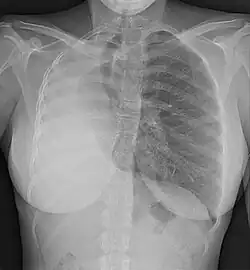

- Lungs, often as a result of oligohydramnios during gestation or the existence of congenital diaphragmatic hernia